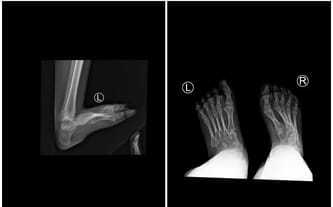

W 34. tygodniu ciąży dowiedziałam się, że Oliwia przyjdzie na świat z przepukliną oponowo-rdzeniową. W jednej chwili radość z mających wkrótce nadejść narodzin dziecka zmieniła się w koszmarny strach. Już podczas pierwszej doby po porodzie odbyła się operacja zamknięcia przepukliny, a po niej kolejne zabiegi mające na celu wszczepienie zastawek. To jednak nie koniec. U córki stwierdzono również stopy końsko-szpotawe, co przyczyniło się do kolejnych operacji m.in. wydłużenia ścięgna Achillesa.

W pierwszej kolejności planowana jest operacja lewej kończyny dolnej obejmująca rekonstrukcję biodra, stawu kolanowego oraz skokowego. Rehabilitacja w obrębie stawu kolanowego rozpocznie się już następnego dnia po zabiegu. Po kilku kolejnych tygodniach córkę czeka jeszcze operacja prawego stawu kolanowego.